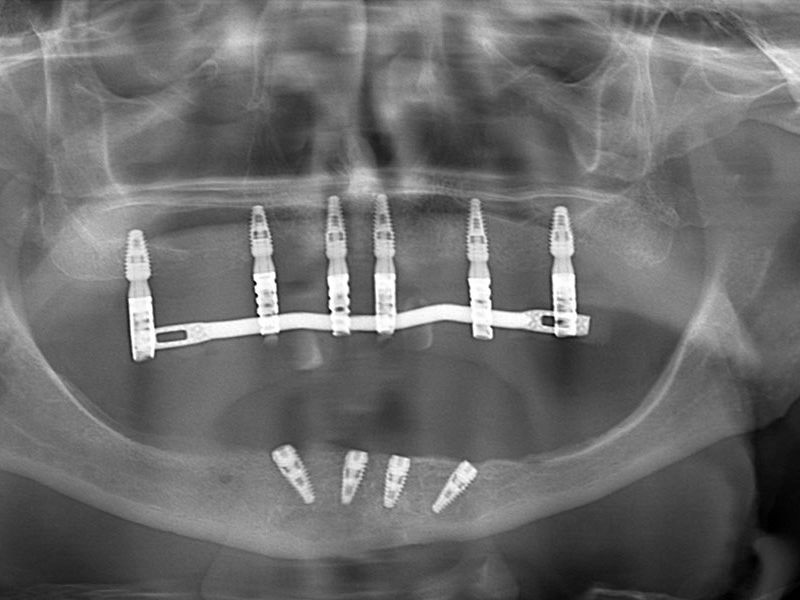

6 dental implants

6 abutments

• This operation is carried out after the panoramic and CT scan of the patient's dental arches;

Performed treatments